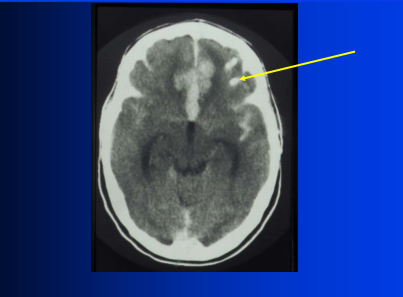

Top: bilateral PCA infarcts from emboli can often become hemorrhagic (and can be multifocal)

Bottom: small clot/embolus (arrow) with surrounding hemorrhagic infarct